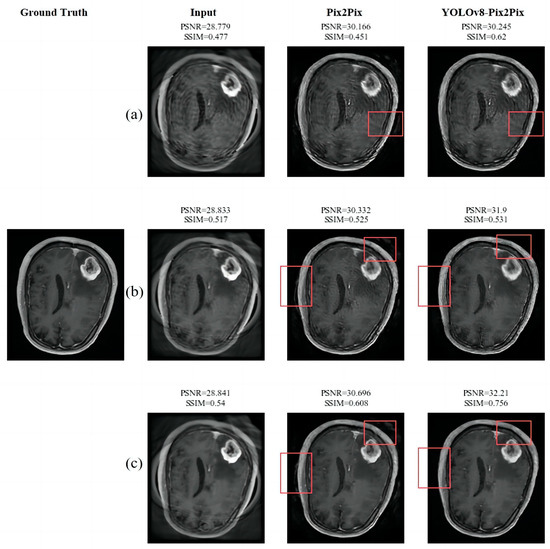

3.3.1. The Experimental Results and Analysis of the Removal of Artifacts

| TR | Gaussian Filter | Cyclegan | Pix2Pix | YOLOv8 | YOLOv8-Cyclegan | YOLOv8-Pix2Pix | |

|---|---|---|---|---|---|---|---|

| PSNR | 28.918 | 28.821 | 29.998 | 30.421 | 29.113 | 29.568 | 31.459 |

| SSIM | 0.566 | 0.526 | 0.571 | 0.612 | 0.491 | 0.513 | 0.650 |